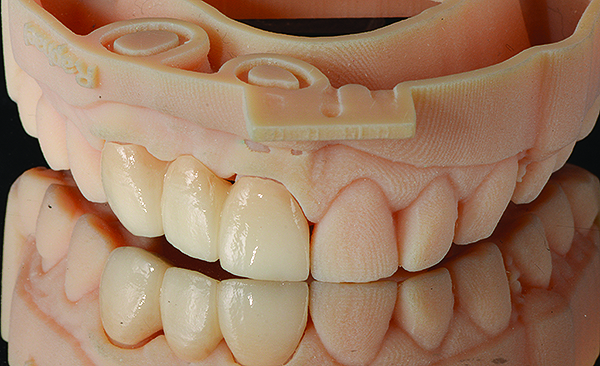

(3.) Digital mock-up of prosthesis replacing missing incisor.

Figure 3